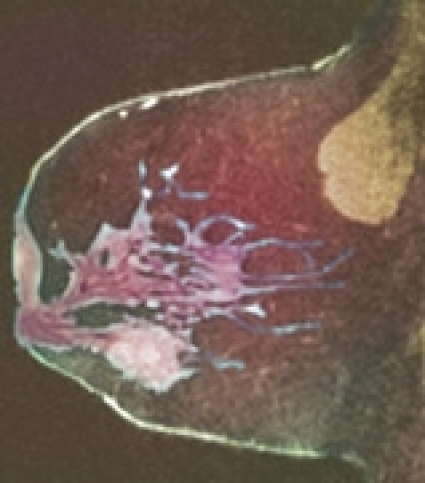

I Storbritannien har 22 ackrediterade bröstenheter utvärderat MRT som tillläggsmetod för screening av högriskkvinnor och funnit metoden användbar. Anlagsbärare eller de med en beräknad årlig incidensrisk på 0,9 procent inkluderades. En knapp femtedel var kända anlagsbärare. Alla undersökningar dubbelgranskades. 649 kvinnor deltog. Bortfallet under sjuårsperioden var cirka 20 procent bla på grund av riskreducerande kirurgi, genetiska testresultat, bröstcancerdiagnos och obehag av MRT. MRT hade högre sensitivitet (77 procent) än mammografi (40 procent) oavsett om kvinnorna var anlagsbärare eller inte. Kombination av MRT och mammografi gav ännu högre sensitivitet (94 procent) på bekostnad av lägre specificitet (81 procent). Man upptäckte 35 fall av cancer, 19 med MRT, 6 med mammografi, 8 med båda teknikerna och 2 fall av intervallcancer.

»Kostnaden« inbegrep att 4 procent återkallades årligen på grund av mammografifynden och 11 procent på grund av MRT-fynden. I 3 procent av fallen krävdes operation för att bekräfta eller utesluta malignitet. Tumörerna var i medeltal 15 mm och körtelnegativa. 6/35 var duktal cancer in situ.